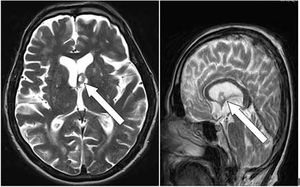

Case History: 15-month-old with focal seizure, developmental delay, disproportionate increase in size of head.